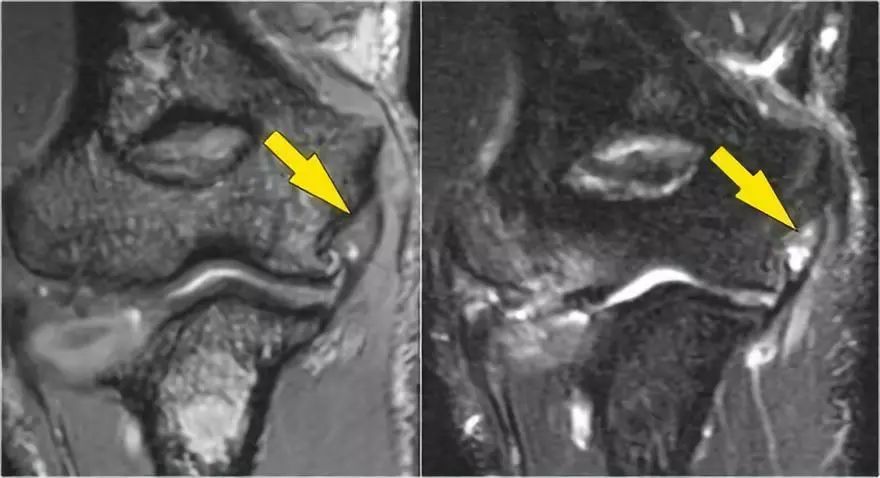

外翻过度综合征的关节病由于外翻过载,在肱骨-尺骨关节的后内侧部分存在剪切力。注意在T1W图像上看到的软骨下硬化(红色箭头)。在T2W图像上存在软骨下骨髓水肿和软骨损失(黄色箭头)。